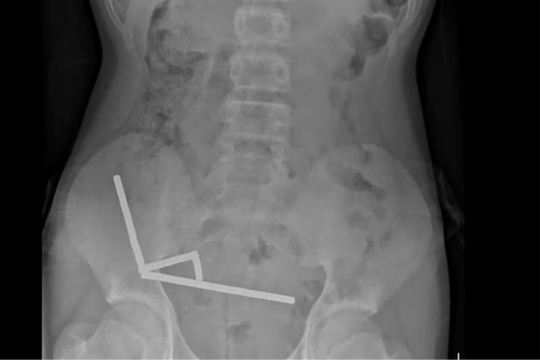

Thoát nguy cơ liệt tứ chi sau ca phẫu thuật trật đốt sống cổ hiếm gặp

03/11/2025 07:43

Các bác sĩ vừa phẫu thuật thành công ca trật đốt sống cổ C45 hiếm gặp cho bệnh nhân 67 tuổi, giúp người bệnh thoát nguy cơ liệt tứ chi và hồi phục hoàn toàn vận động.